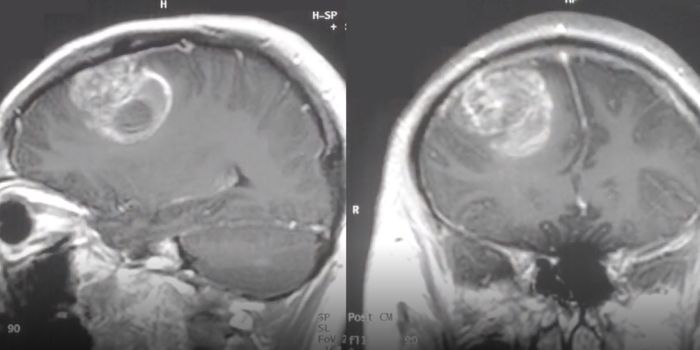

JAN 12, 2021Cell & Molecular BiologyThe most common and deadly form of brain cancer is known as glioblastoma; the median survival time for patients is only ...